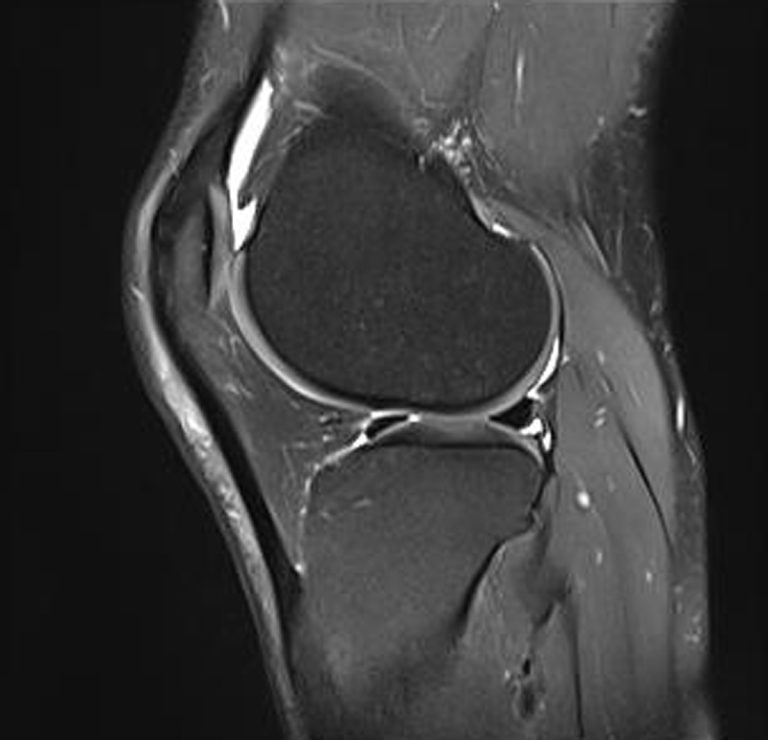

Drei Tage später habe ich wieder einen Termin, diesmal in der Nachbehandlung auf der Handambulanz. Samt Gips komme ich ins CT. Beim Warten davor erzählt mir ein anderer Patient, dass Radiuskopfbruch 6 Wochen Gips und 6 Monate Physio bedeutet. Ich will es nicht so recht glauben. Nach dem CT komme ich in die Nachbehandlung. Die Ärztin schaut verwundert das CT an und vergleicht es mit dem 3 Tage alten Röntgen. Das Bruchstück ist “von alleine” wieder an seine ursprüngliche Stelle gewandert! Nun ist der Abstand weit unter 1 Millimeter. Es ist leicht verdreht, aber grundsätzlich richtig positioniert. Sie telefoniert lange mit anderen Ärzten wie nun zu verfahren sei. Sie lässt mir den Gips abnehmen und die Beweglichkeit des Ellbogens ist sehr gross (30 Grad Stecken und 100 Grad Beugen). Bei diesem Umstand telefoniert die Ärztin abermals mit Kollegen. Sie erklärt mir anschliessend, dass dieses “Zurückwandern” des abgebrochen Radiusköpfchens sehr selten vorkommt (1 von 10000 Mal) und sie mir deswegen den Gips nach nur 3 Tagen definitiv abnimmt und mir eine art Exoskelett verordnet. Es heisst richtig Orthese, weil es eine passive aussen anliegende Schiene ist. Sämtliche Drehbewegungen werden unterbunden und die Beugung des Ellbogens wird auf die 30 und 100 Grad fixiert. Nur zum Rausgehen und zum Beschaffen der Schiene wird mir der Gips wieder angelegt.

Zwei Wochen später habe ich wieder einen Kontrolltermin auf der Klinik. Es wird wieder ein Röntgen gemacht. Dieses bestätigt, dass das lose Stück nach wie vor gut positioniert ist und langsam anwächst. Diesmal ist wieder ein anderer Arzt zugegen. Er lässt mich die Schiene abnehmen und den Arm bewegen. Es geht nicht viel mehr als zwei Wochen davor. Auch er grübelt länger über den Röntgen- und der CT-Aufnahme. Und befindet anschliessend, dass ich auch die Schiene ganz weglassen kann! Ich bin etwas unsicher und schnalle sie am Heimweg wieder um. Ich soll den Arm nun vier Wochen immer nur bis zur Schmerzgrenze bewegen und keinesfalls irgendwie belasten. Es beleibt offen, ob ich eine Physiotherapie machen muss.

Am Montag den 23. Februar 2026 fahre ich unangemeldet auf die Klink Innsbruck und klagte mein Leiden. Man nimmt mich auf und machte wieder Röntgen aus drei Winkeln. Doch hier ist alles in Ordnung. Die Ärztin meinte, es ist durch das Stecken wohl das junge noch nicht ganz feste Knochengewebe touchiert worden und dies fühlt sich an wie eine Prellung. Vom Gefühl kommt das hin, aber was erzeugte das Knacken? Weichteile sieht man im Röntgen natürlich nicht sichtbar und im MRT/CRT wären kleinste Weichteile ebenso schwer zu erkennen. Die Ärztin meinte jedenfalls, die Physiotherapeutin solle sachter rangehen. Faktisch bedeutet das leider gerade einige Wochen Rückschritt in der Genesung.